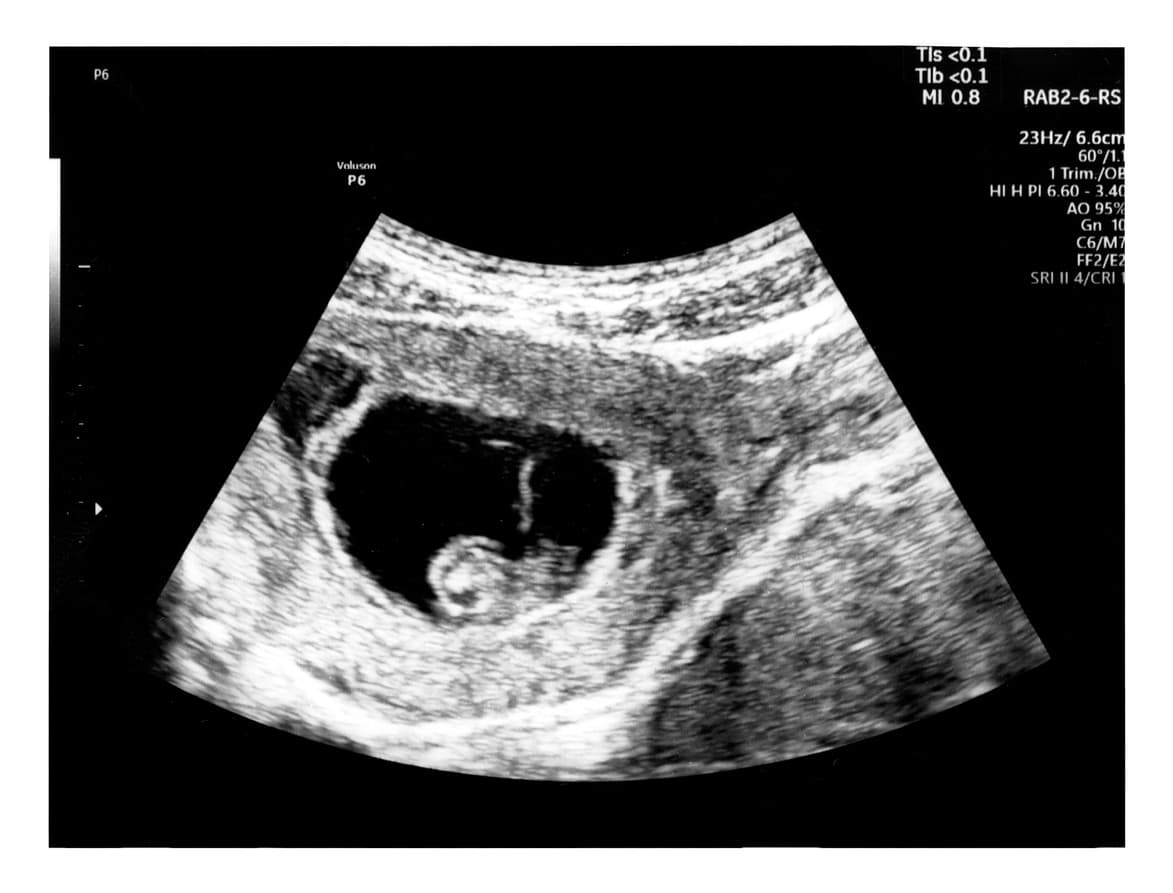

Los especialistas de National Health Service explican que un embarazo molar o mola hidatiforme sucede cuando hay una fertilización anormal del óvulo, generando que el bebé y la placenta no se desarrollen como debería.

MedlinePlus describe que el embarazo molar se ve como una masa cubierta por moras, ya que contiene muchos quistes pequeños.